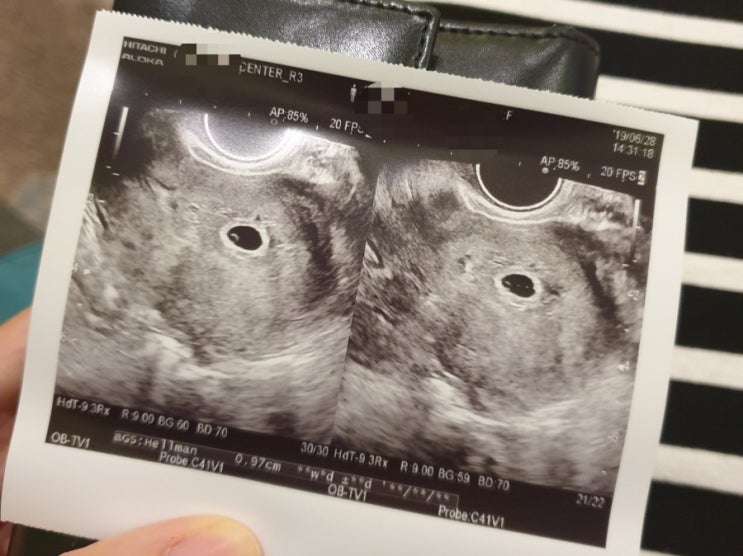

임신 30주 / 초음파, 배크기, 임산부 백일해 주사 예방접종

30주 초음파 임신 30주 정기검진 있는날 항상 설렌다. 우리 아기 얼마나 컸을까.. 30주 뿡뿡이는 골격이 거...